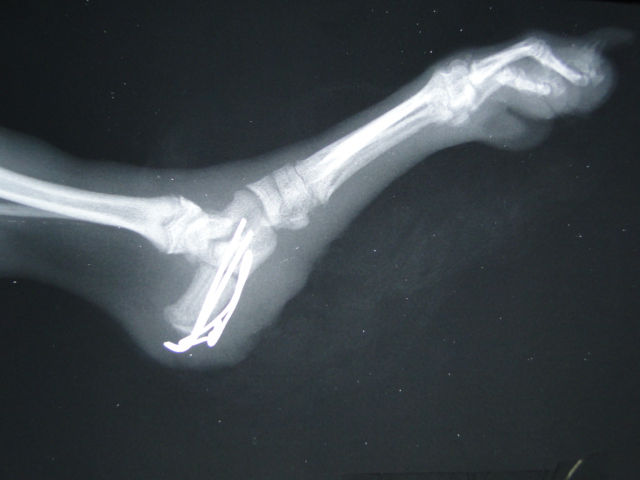

●キャスパー 6カ月 チワワ ♂

他院のご紹介で来院されました。飼い主さんが気が付いた時には、足を上げていたそうです。飼い主さん曰く「ソファーから落ちたのではないか?」との見解ですが、落下で生じる骨折ではないので、誰かに踏まれた可能性があります。キャスパーはとっても大人しくて良い子なので、踏まれても声をあげず我慢していたのではないかと予想されます。右の写真では、「左のかかと」が横にずれているのが分りますか?骨折して間もないので、随分と腫れています。

●手術

折れた踵を元に戻して、2本のピンとワイヤーで固定しました。1.6kgしかない小さな子犬でしたので、手術スペースが少なく、さらに、若いので危弱でした。

●レントゲン写真

手術後、確認のために、レントゲン写真を撮影します。